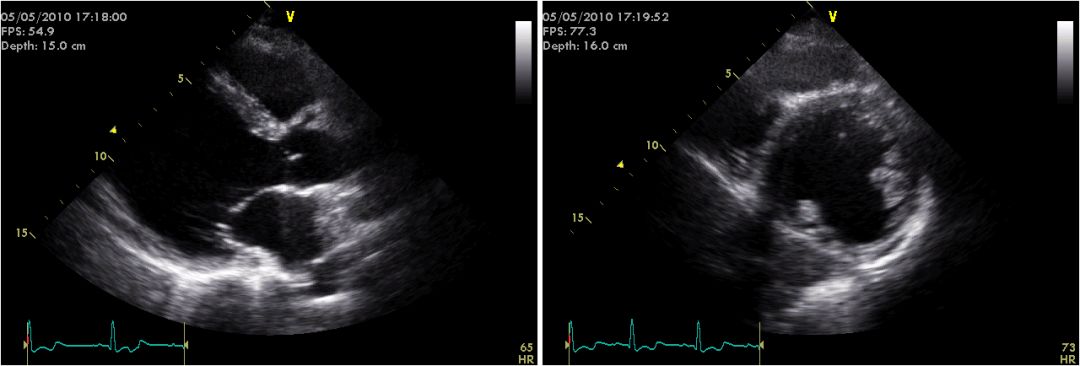

外院ECHO:扩张型心肌病,左房、左室扩大,左室舒张、收缩功能降低,二尖瓣少量返流,EF27- 45%。

节段性运动异常

治疗前

2个月后

激素及抗心衰治疗后